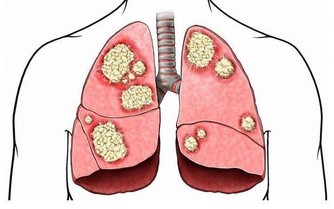

我們都知道,腎臟是身體最大的排泄器官,將體內的廢物毒素排出,與我們的身體健康有著重要的聯繫。